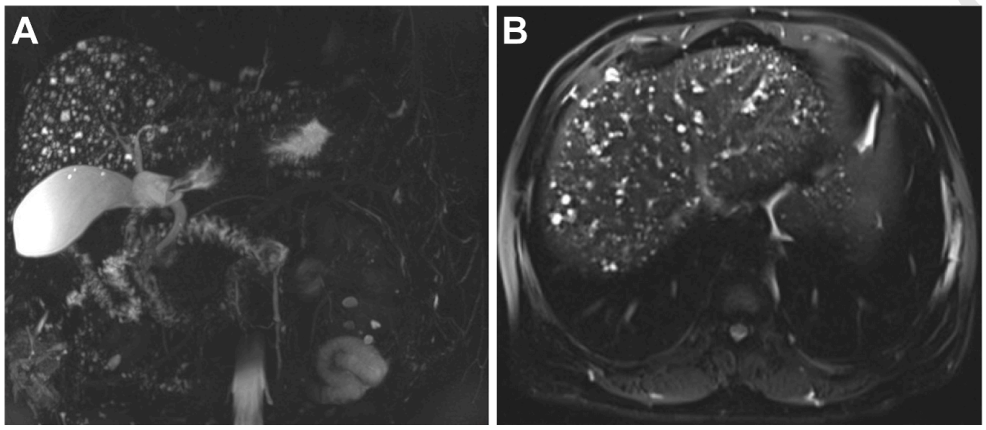

病史摘要:33岁女性患者,数月来右上腹间歇性不适,伴早饱、腹胀及恶心,症状反复后就诊。 诊疗过程:体格检查无明显异常。实验室检查肝功能及肿瘤标志物正常,尿妊娠试验阴性。腹盆部增强CT见肝内3个不明病灶;腹部MRI显示病灶有包膜皱缩、弥散受限等特征,出现“棒棒糖征”。主要诊断为肝上皮样血管内皮细胞瘤(EHE),鉴别排除转移瘤等疾病。经皮穿刺活检病理及免疫组化确诊EHE。随访8个月病灶大小